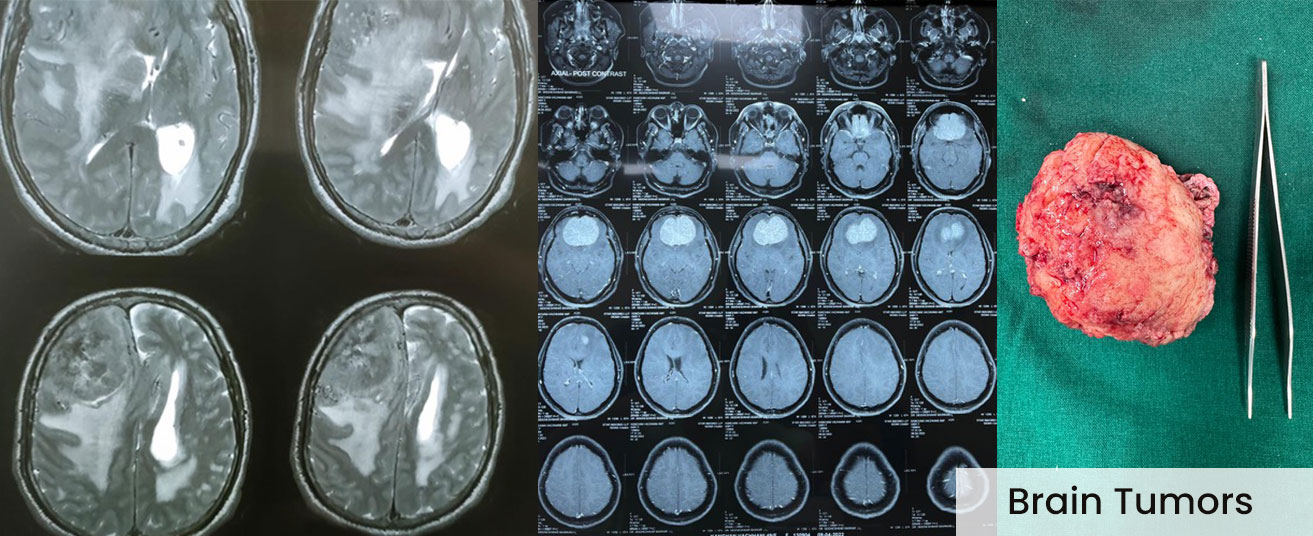

Brain and spine tumors such as gliomas, meningiomas, metastatic brain tumors, and spinal cord tumors can significantly impact health and quality of life. Dr. Yeole’s precise surgical skills, supported by advanced technology, help improve outcomes and minimize risks.

They are usually detected by thorough clinical assessment followed by MRI, CT scans, and other advanced imaging techniques.